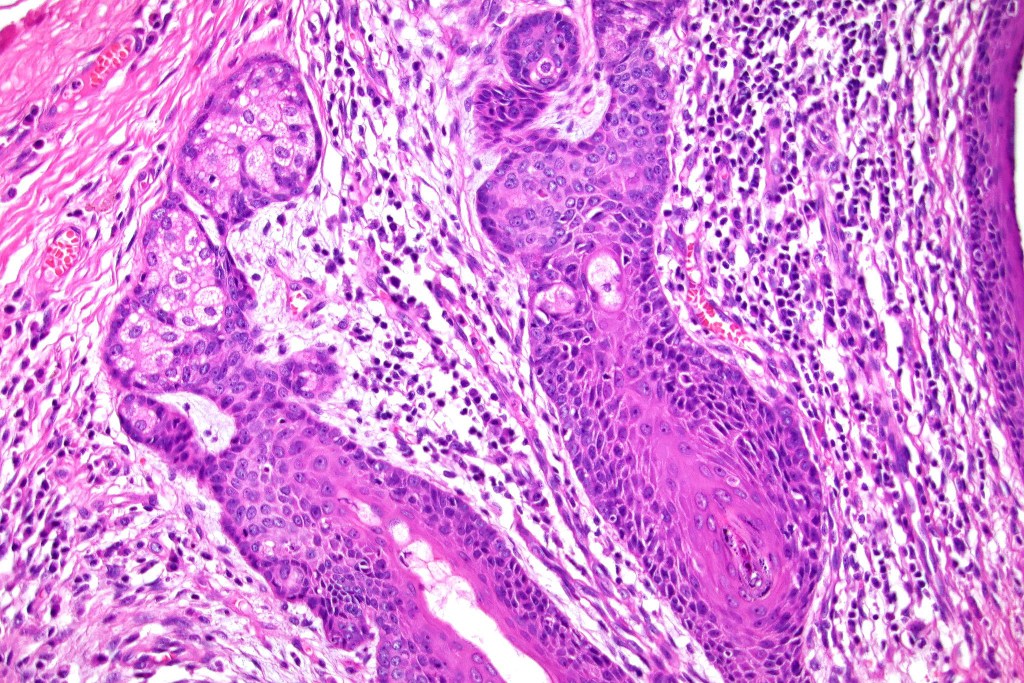

•Variably sized but generally large, basophilic tumor nodules composed of small uniform basaloid cells with minimal cytoplasm

•Variable mitotic activity, can be brisk

•No pleomorphism or abnormal mitoses

•Peripheral palisading but no retraction artifact or stromal mucin deposition